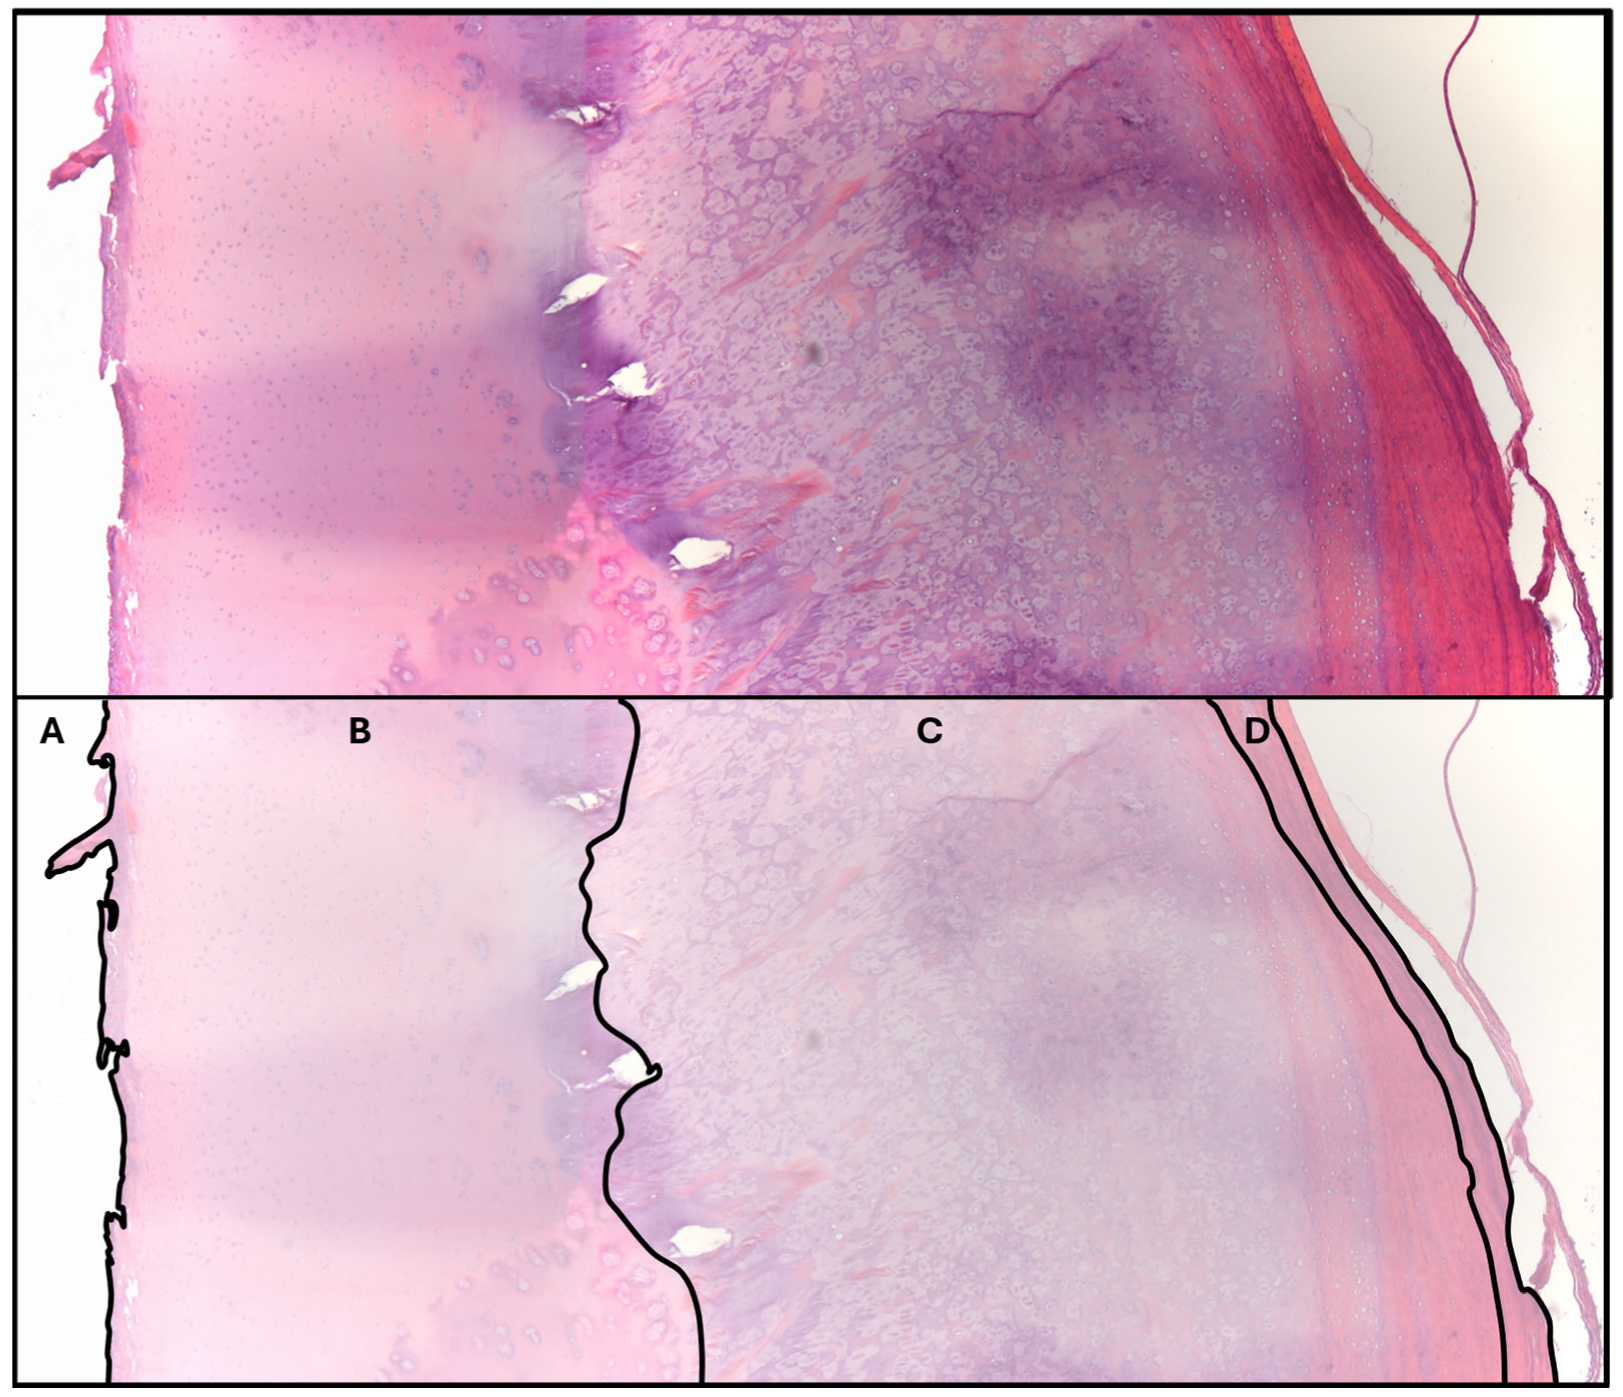

3.2.3. Histology of Intra-Articular Fragment

3.3.2. Histopathologic Data